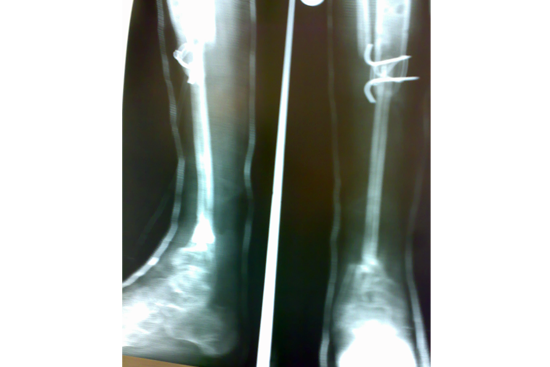

Tibialisation of Fibula

Method

We have done Huntington technique by stage ilizarov procedure. Here is the diagrammatic representation of our method.